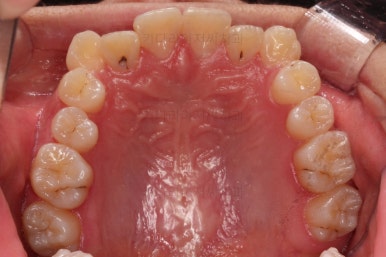

충치가 곳곳에 보이는데요.

성인들은 충치가 멈춰있는 정지우식일 가능성도 있으며 크기가 현재 크지 않고 향후 변화되지 않는다면 그대로 두기도 합니다.

이번 환자분도 교정치료에 방해되는 부분이나 급해보이는 추료만 우선 진행하고 교정 중에 충치가 커지는지 증상이 생기는지 관찰해 보기로 했습니다.

입 안을 보면 밑에 치열이나 다른 부분은 비교적 양호한데 유달리 윗니 송곳니만 위치가 좋지 못하네요.

이번 환자분은 보기에는 송곳니가 덧니라 많이 삐뚤어 있는 것 같지만 치료는 비발치, 즉 발치 없이 진행했는데요.

삐뚤다는 건 자리가 부족하다는 뜻인데 부족한 자리를 확보 안해주고 억지로 가지런하게 하다보면 치아가 앞으로 튀어나오게 되거든요.